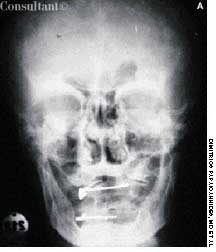

A 29-year-old woman is brought to the emergency department after a caraccident. She complains of head pain and has a contusion over the posterioraspect of the right temporal bone and right occipital bone; a small amount ofblood flows from the right external auditory canal. She has only a vague recollectionof the accident. Past medical history-although difficult to ascertain-seems noncontributory.